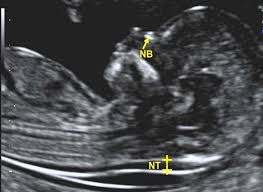

Permite evaluar la presencia de marcadores asociados a alteraciones cromosómicas en el feto, ayudando en la detección temprana de síndromes genéticos.